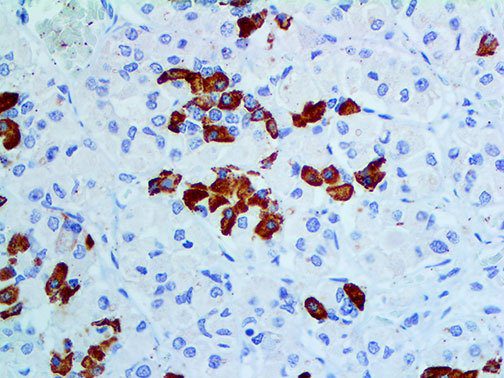

It is the ICU physician who is most likely to witness one of the deadliest manifestations of the abnormal immunological response, the cytokine storm syndrome (CSS). This response is also referred to by some as the cytokine release syndrome (CRS). CSS is characterized by continuous activation and expansion of macrophage and lymphocyte populations, which secrete large amounts of cytokines, causing the cytokine storm. This massive cytokine release is akin to hemophagocytic lymphohistiocytosis (HLH) disease, a syndrome characterized by initial unchecked and persistent activation of cytotoxic T lymphocytes and NK cells.

Clinical and laboratory manifestations of HLH include fever, enlarged liver and/or spleen, neurologic dysfunction, coagulopathy, liver dysfunction, cytopenias (i.e., low levels of erythrocytes, leukocytes, and/or platelets), hypertriglyceridemia, hyperferritinemia, hemophagocytosis, and eventually diminished NK cell activity as the immune system becomes progressively paralyzed. HLH can be familial (primary HLH) or secondary to another disease process (sHLH), such as rheumatic disease, in which it is referred to as macrophage activation syndrome (MAS, characterized by elevated ferritin).